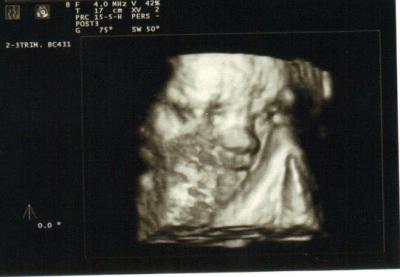

Sehr quirlig ist er jedenfalls auch, es vergeht keine Stunde, die er nicht mitteilt, dass er da ist (auch nachts). Er bewegt sich eben gern und viel. Einerseits freut und das, andererseits bekommen wir nie eine vorzeigbare 3D-Aufnahme, weil durch die Bewegungen zu viele Unschärfen entstehen.

Eine kurze (nur leicht unscharfe) Momentaufnahme haben wir dennoch festgehalten. Das Stupsnäschen kann man jedenfalls gut erkennen.